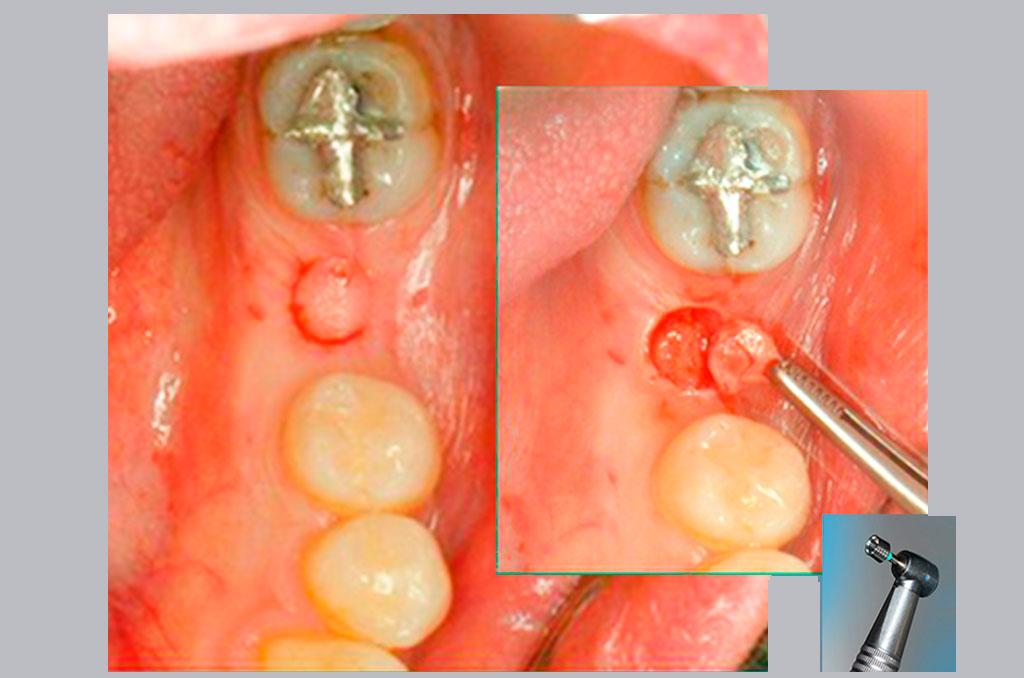

En este sentido nuestro consultorio desarrolla desde 1999 la técnica flapless prescindiendo del bisturí convencional y sin sutura, a través de una incisión circular de 5 mm de diámetro que garantiza un postoperatorio que pasa inadvertido y logra excelente resultado estético.

La técnica quirúrgica flapless (sin solapa) posee varias ventajas comparada con los procedimientos quirúrgicos convencionales, que incluyen la apertura de una solapa (flap) antes de la inserción del implante.